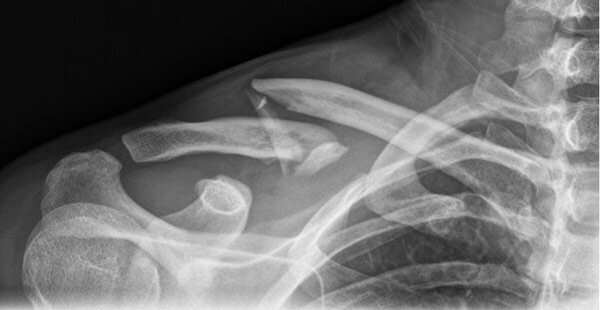

Рентгенография ключицы

Рентген ключицы – это 2-х мерный рентгеновский снимок, включающий в себя ключицу, а также грудино-ключичное и ключично-акромиальное сочленения.

Рентгенография ключичной кости позволяет визуализировать костную ткань. Нередко проводят профилактический рентген здоровой ключицы, который позволяет выявить заболевания плечевого пояса на ранней стадии развития. Такой подход рекомендуют пациентам, которые регулярно подвергаются физическим нагрузкам:

• Трещины и переломы кости;

• Остеофиты и другие новообразования;

• Врождённые дефекты;

• Аномалии строения и развития.